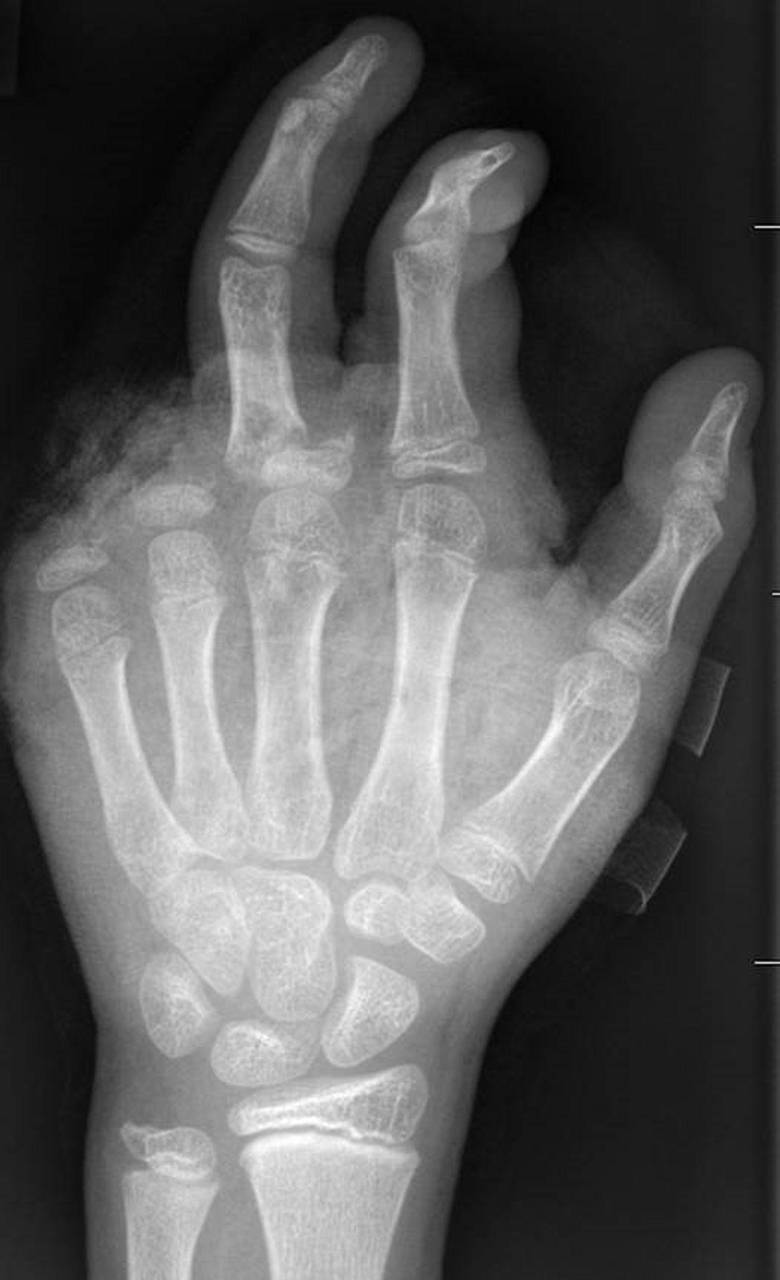

Böller-Verletzungen

Berlin (dpa) - Abgetrennte Finger, durchtrennte Sehnen, Amputationen - die Handchirurgin Leila Harhaus-Wähner hat in der Silvesternacht schon vieles gesehen. Auch in diesem Jahr rechnet die Berliner Ärztin mit zahlreichen Böller-Verletzten. «Für Handchirurgen ist es klar, dass Silvester die arbeitsreichste Nacht sein kann.» Bis 24 Uhr passiere erstmal nicht so viel, ab 1 Uhr, 2 Uhr nachts kämen immer mehr Verletzte in die Notaufnahme und dann «sehr viele in sehr kurzer Zeit.»

In der Handchirurgie müssten an Silvester im Unfallkrankenhaus rund 20 bis 40 Menschen mit Böllerverletzungen operiert werden, sagt die Ärztin. Dieses Jahr werde sie mir vier weiteren Handchirurgen im Einsatz sein. Die häufigsten Verletzungen entstünden durch explodierende Böller in der Hand.

«Der überwiegende Teil der Verletzungen trägt tatsächlich lebenslange Folgen mit sich, weil die Sprengkraft dazu führt, dass eben nicht nur einzelne Strukturen verletzt sind, sondern immer mehrere. Und das heilt praktisch nie ganz folgenlos ab.» Zum Teil könnten Hände nicht mehr gerettet und müssten amputiert werden.